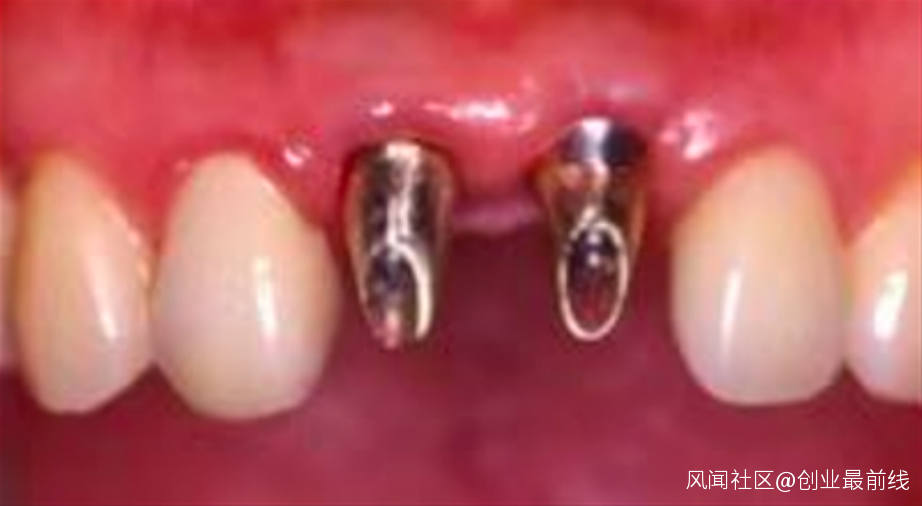

(圖 / 患者植入植體 本圖版權為禎諾ZENOIS,由好牙醫提供)

(圖 / 患者種牙效果 本圖版權為禎諾ZENOIS,由好牙醫提供)